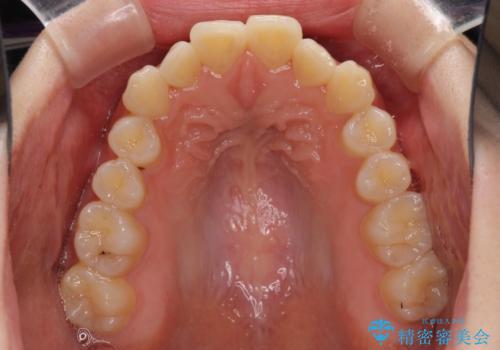

- 上の前歯が出っ張っている気がするとのことで来院された患者様です。

急いで治す必要性がないとのことで、自分のペースでのんびりと治療を行えるインビザラインにて矯正治療を行うこととしました。

半年もせずにインビザラインを全く使用することができなくなってしまったので、治療開始から1年ほどでワイヤー矯正へ変更することとなりました。